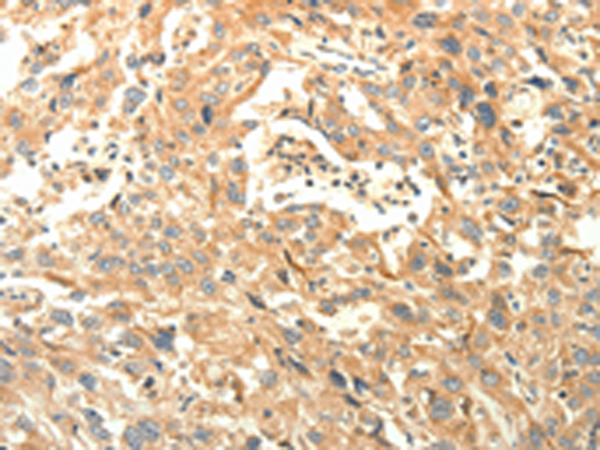

分类: 科研抗体货号: P11167别名: DSH; AGS6; G1P1; IFI4; P136; ADAR1; DRADA; DSRAD; IFI-4; K88DSRBP应用: IHC反应种属: Human